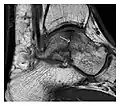

Fatigue fractures are more frequent in women which may be due to the relatively smaller bones of women. Moreover, pregnancy is a well-recognized risk factor for femoral neck fatigue fracture. While fibular and metatarsal fractures have a low risk of complications, other sites including the femoral neck, midanterior tibia, navicular, talar, and other intraarticular fractures are prone to complications such as delayed union, nonunion, and displacement. The site of the insufficiency fracture may be specific to the activity: for example, rugby and basketball players are more prone to navicular fractures, while gymnasts have a higher risk for talar fractures (Figure 7). Long distance runners are at increased risk for pelvic, tibial (Figures 8 and 9), and fibular fractures. In the military, calcaneus (Figure 10) and metatarsals are the most commonly cited injuries, especially in new recruits. Billiard players are at risk for upper limb fractures (Figure 11).[1]

Figure 7: Fatigue fracture of the talus in a 25-year-old male basketball player with right hind foot and ankle pain, without history of trauma, and a normal initial radiograph (not shown). (a) One-month followup lateral radiograph shows normal appearance. (b) Sagittal T1-weighted MRI shows an irregular fracture line (arrow) within an ill-defined area of hypointensity corresponding to bone marrow edema.[1]